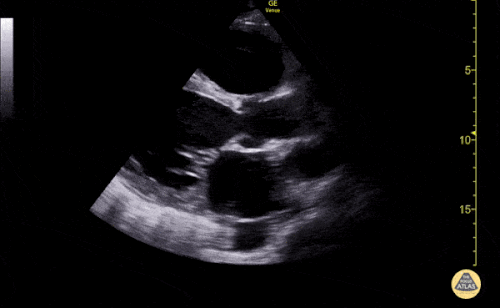

1

Based on the ultrasound image above, which shock etiology is less likely?